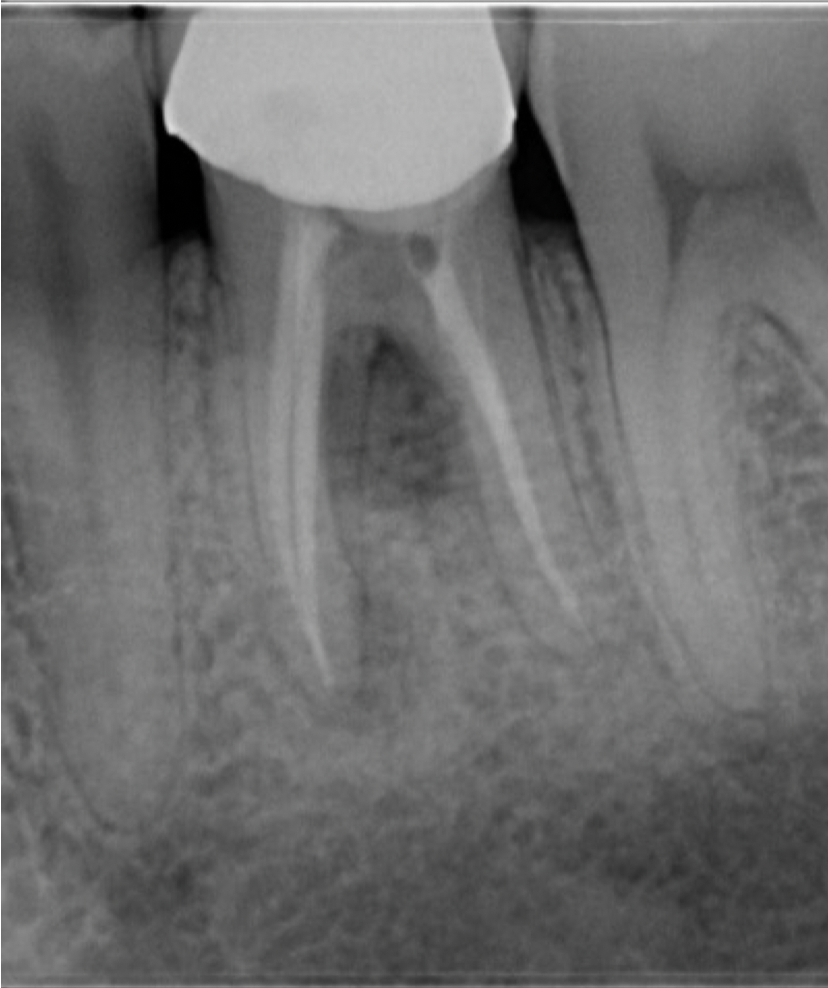

Fig. 7

Radiographic verification of the obturation

Obturation was completed using a single-cone technique in conjunction with a bioceramic sealer, providing a homogenous and biologically favourable seal within the canal system and complementing the previously placed MTA repair (Video 3; Fig. 7).

- Verify obturation radiographically (Fig 7).

Radiographic assessment at follow-up revealed evidence of progressive healing in the furcation region, with no signs of persistent radiolucency or ongoing pathology. These findings suggest favourable biological repair and re-establishment of periodontal integrity.